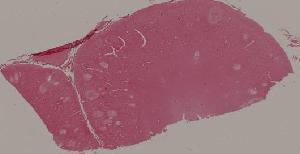

76. Acute pyelonephritis

77. Chronic pyelonephritis

41. Opportunistic infection in the lung

71. Acute transplant rejection of kidney

72. Lupus nephritis

36. Lymphoma

80. Invasive ductal cancer of the breast

84.Graves disease

93. Epidemic cerebrospinal meningitis

94. Encephalitis type B

88. Chronic cavitary tuberculosis of the lung

89. Tuberculous lymphadenitis

90. Lepromatous leprosy of the skin

91. Tuberculoid leprosy

92. Typhoid fever of intestine

95. Poliomyelitis

96. Pulmonary aspergillosis

97. Amebic colitis

98. Schistosomiasis of the colon

99. Experimental acute schistosomiasis of the liver (rabbit)